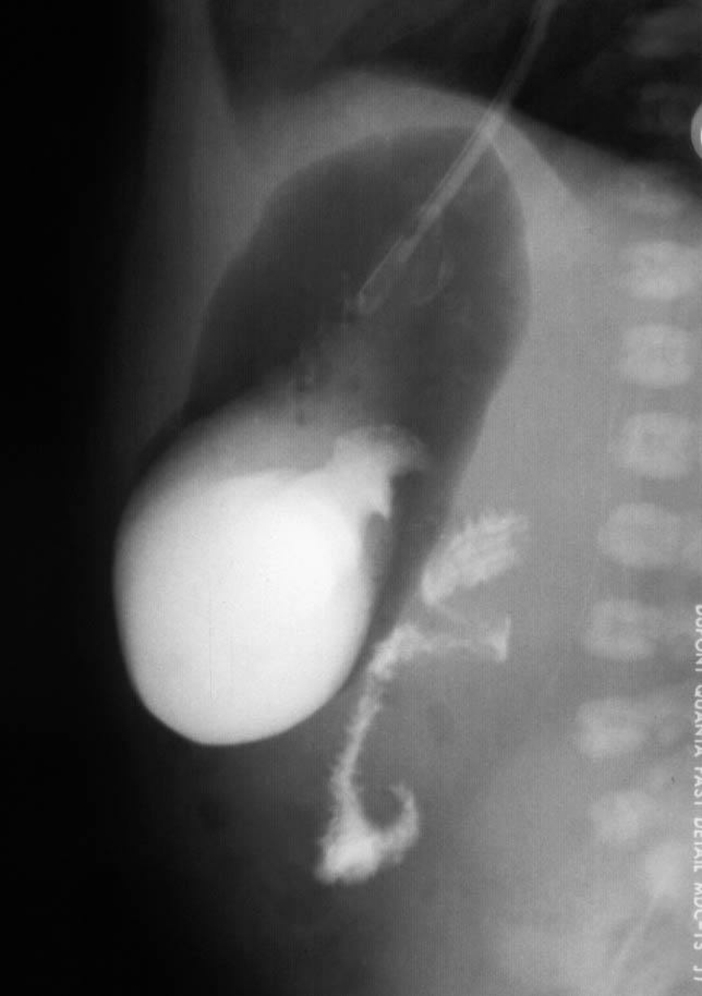

A small luminal opening present in an obstructing diaphragm across the duodenum causes a duodenal web. While the web may allow the liquid diet of infants to pass, the partially obstructed proximal duodenum dilates. Radiographically this manifests as a double bubble with distal gas ( Fig. 4.7A ) and a “wind sock” appearance on contrast studies ( Fig. 4.7B ). These children often experience feeding difficulties when solid food is introduced to the diet or may have complications after an ingested foreign body.

Fig. 4.7, Duodenal web. (A) Radiograph of the abdomen showing “double-bubble”-like dilation of proximal duodenum with gas in distal bowel loops. (B) UGI showing a duodenal web ( arrow ) outlined by contrast in the distended proximal duodenum and adjacent nondistended duodenum.